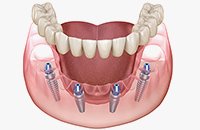

オールオン4 All-on-4

オールオン4は、4本のインプラントで上顎または下顎の人工歯列を支える方法です。従来の多数本インプラントよりも少ない本数で治療できるため、身体的負担や治療期間、費用を抑えられることが特徴です。

オールオン4では、インプラントを斜めに埋め込むことで噛む力を広く均等に分散し、最小4本のインプラントで上顎または下顎の全ての人工歯を支えることができます。日帰りで手術が可能なため、患者さまの身体的な負担も軽減され、手術当日に仮歯を装着できます。わずか1日で口元の機能と見た目が改善され、これまでの歯に関する悩みから解放されます。多くの歯を失った患者さまにとって、治療にかかる時間や費用、身体の負担を最小限に抑えながら、安定した噛み心地と自然な見た目を実現できる治療法です。